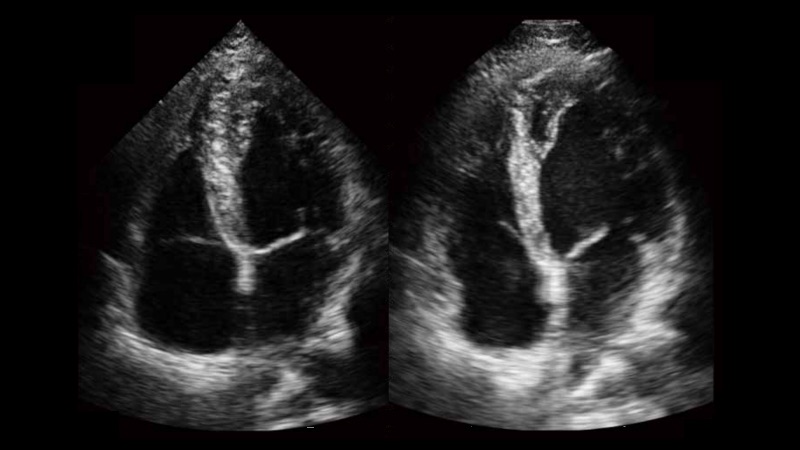

自動(dòng)識(shí)別前后壁內(nèi)膜厚度,為心血管疾病早期評(píng)估提供快速準(zhǔn)確依據(jù)。

自動(dòng)識(shí)別收縮和舒張末期心肌內(nèi)膜,自動(dòng)計(jì)算射血分?jǐn)?shù)EF值。